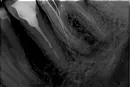

В 2009 году тридцать шестой зуб депульпировали и запломбировали каналы. Чем - не знаю. В начале февраля он стал немного беспокоить, решили открыть каналы, но не смогли. Вроде как тонкий канал и инструмент ушёл в сторону. С временной пломбой (оставляли внутри эвкалиптовое масло), зуб болел невыносимо, не помогали никакие полоскания, попросила открыть. Открытый (на время еды закрываю ватой) не болит вообще, даже без полосканий. Врач говорит, что канал пройти не сможет, следовательно, зуб подлежит удалению. Соседние зубы еще хуже, цеплять на них что-то будет проблематично, а с имплантацией связываться не хочется по своим соображениям. До сих пор все зубы свои, хотя большинство пломбированные.

Прикрепленые фото

В зубе имеется воспаление, которое теоретически пролечить невозможно, к тому же горе-врачи перфорировали вам корень зуба и после этого зуб удивляется однозначно. Не переживайте и не бойтесь имплантации, это просто и не больно, и реабилитации нет, если процедуру выполняет опытный хирург. Не торопитесь удалять зуб, приезжайте, ваши показания говорят о возможном одномоментном удалении и установки имплантата.